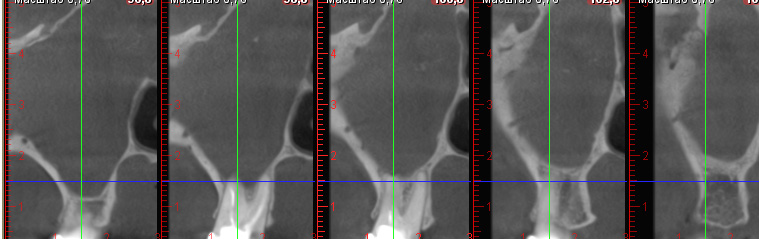

Пациент С. МСКТ выполнялась в предоперационном периоде. По результатам исследования получено следующее заключение: участки фиброзной остеодисплазии левой ВЧП, левая ВЧП гипоплазирована, деформирована, в переднем отделе пазухи костная перемычка, в полости ВЧП небольшой объем жидкости, неравномерная гипертрофия слизистой, гаймороназальное соустье не определяется (рис. 6). Интерпретация данных врачами-оториноларингологами расценивалась в объеме агрессивного хирургического вмешательства с широким операционным доступом с вовлечением костных структур верхней челюсти.

Рис. 6. Пациент С., предоперационное КЛКТ, вид ВЧП слева

По данным КЛКТ визуализировано: отсутствие дистрофических изменений соединительнотканных структур, левая ВЧП гипоплазирована, деформирована, в переднем отделе пазухи костная перемычка, в дистальной трети дна ВЧП визуализировано новообразование, вероятнее всего, истинная киста ВЧП диаметром 13,46 мм, гаймороназальное соустье не определяется (рис. 7).

Рис. 7. Пациент С., предоперационное КЛКТ, вид ВЧП слева

После проведения КЛКТ пациенту установлен диагноз: обострение хронического верхнечелюстного синусита слева, киста ВЧП слева. В условиях местной анестезии пациенту выполнялось малоинвазивное дренирование ВЧП с цистэктомией и формированием гаймороназального соустья.